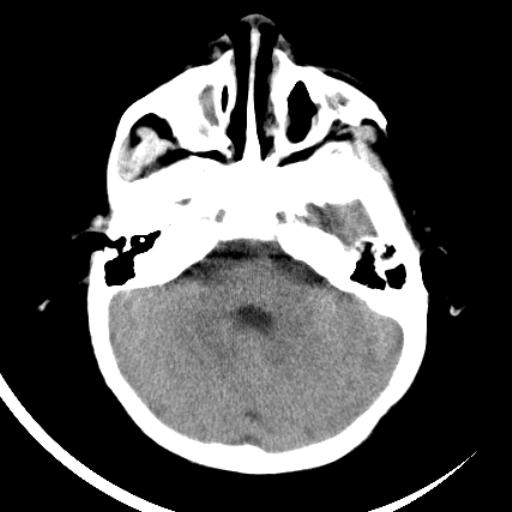

双侧脑室前后角周围白质片状低密度影,双侧侧脑室旁、双顶叶皮层及皮层下多个小原点状钙化灶,不除外torch感染。右顶叶脑回似乎较对侧大,建议mri检查以除外脑发育异常。

考虑:1、巨脑回畸形(皮质明显增厚+脑回明显增宽+白质减少)。

2、torch综合征(室管膜下钙化+白质内及皮髓质交界处多发钙化)。